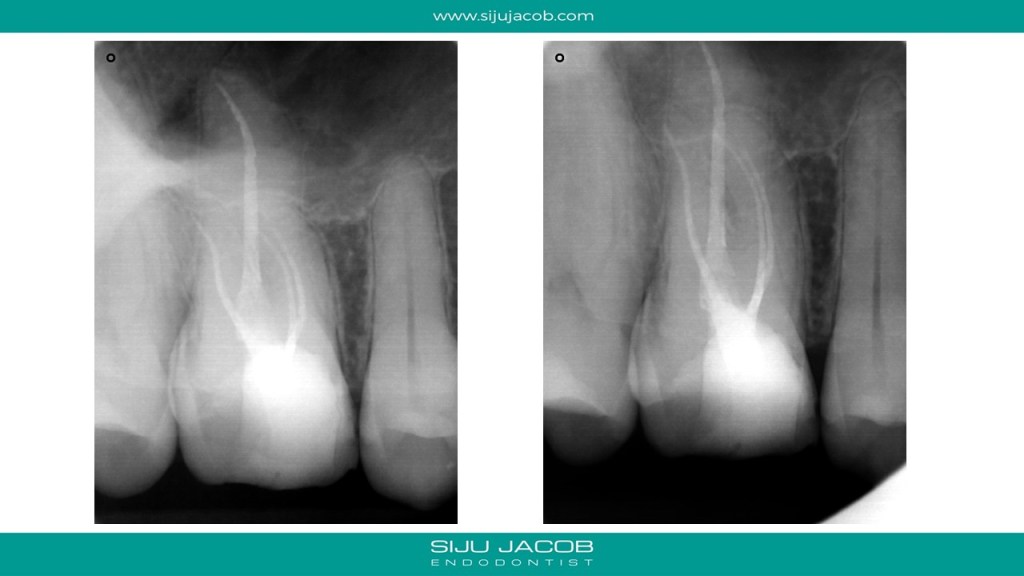

The one thing that has changed over the past few years is that I have become comfortable with skinny shapes. Earlier, we used to strive to achieve those classic “Schilder shapes”. Off late, I’m okay in some cases to end with even a 2% taper. This case is an example